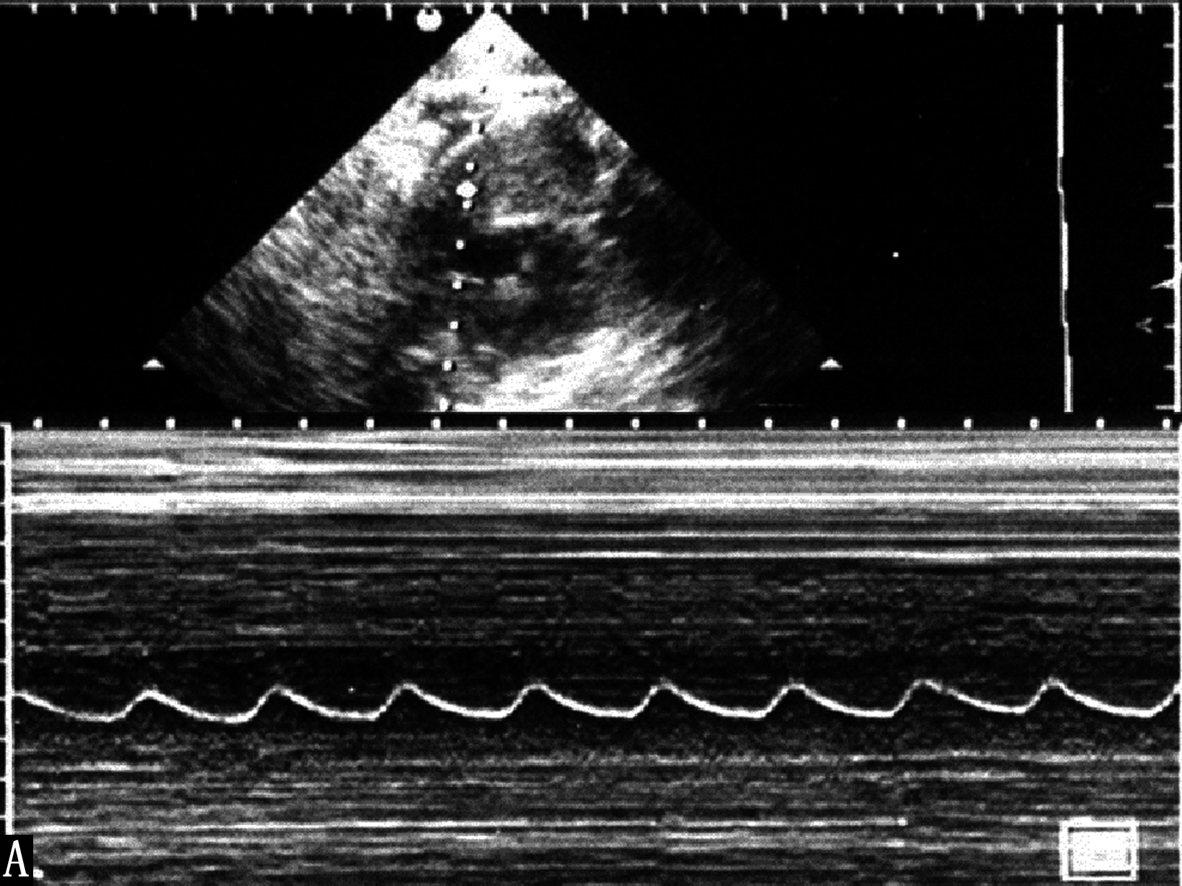

胎儿心律不齐并不少见,但病理性的心律不齐比较少见。和小儿一样,最常见的是窦性心律不齐和早搏。利用胎儿超声心动图和胎儿多普勒超声心动图可以很容易地记录胎儿心脏的异常搏动(图2A-C),并且由于心脏的异常搏动引起的异常血流频谱较心脏活动曲线更容易辨认,但能够提供给临床有价值的信息比较少。根据异常搏动对心室射血的影响程度以及代偿间期有时可以分辨异常搏动的来源,由于胎儿心率较快,分辨时多数有一定的困难。母亲因素,如情绪波动过大、疾病、饮酒、浓茶、过量的咖啡、子宫收缩等,胎儿的因素,如脐带受压、胎儿宫内窘迫、胎儿心脏畸形等均有可能引起胎儿心律失常。发现胎儿心律不齐时应密切观察复查,以判断其临床意义。严重的、持续存在的心律不齐,尤其是严重的室性心律不齐、阵发性心动过速等,可能由胎儿心脏的异常所致。缓慢而不规律的胎心活动常是胎儿凶兆之一。Copel等研究了来自4838个胎儿的5566份胎儿心脏超声检查记录。在595例心律不齐的胎儿中,330例(55.4%)没有发现异常,255例(42.9%)早搏,余10例的心律不齐对胎儿的血流动力学产生了一定的影响,其中9例预后良好,仅有2例合并有心脏发育异常。

图2-B胎心活动曲线记录的异常早搏(左:箭头)及胎心活动曲线记录的二联律(右箭头)